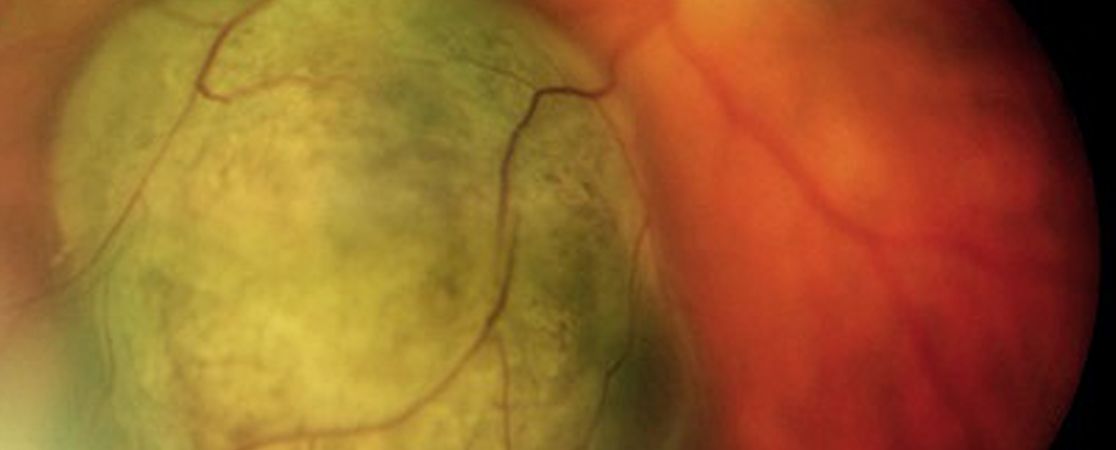

In der Aderhaut des Auges können Absiedlungen von Tumoren anderer Organe entstehen. Die Aderhautmetastase ist insgesamt der häufigste bösartige Tumor im Augeninneren. Beim Mann ist der häufigste zugrundeliegende Tumor das Lungenkarzinom, bei der Frau das Brustkarzinom. Es folgen Metastasen von Tumoren des Magen-Darm-Traktes, der Nieren oder von Karzinoiden. Die Metastasen im Augeninneren fallen dem Betroffenen erst bei Beeinträchtigung der Sehachse durch das Tumorgewebe oder die begleitende Flüssigkeitsansammlung unter der Netzhaut auf. Sie kommen in einem drittel der Fälle mehrfach in einem Auge vor und sind in einem drittel der Fälle in beiden Augen zu finden.

Aderhautmetastasen wachsen im Allgemeinen recht schnell, so dass sie auch einer zügigen Therapie zugeführt werden sollten. Die Behandlung erfolgt immer in Zusammenarbeit mit onkologisch und strahlentherapeutisch Betreuenden. Die Therapie des zugrundeliegenden Tumors kann eventuell schon zur Rückbildung der Aderhautmetastasen führen. Die fraktionierte externe Bestrahlung führt in den meisten Fällen zu einer guten Regression der Metastasen.